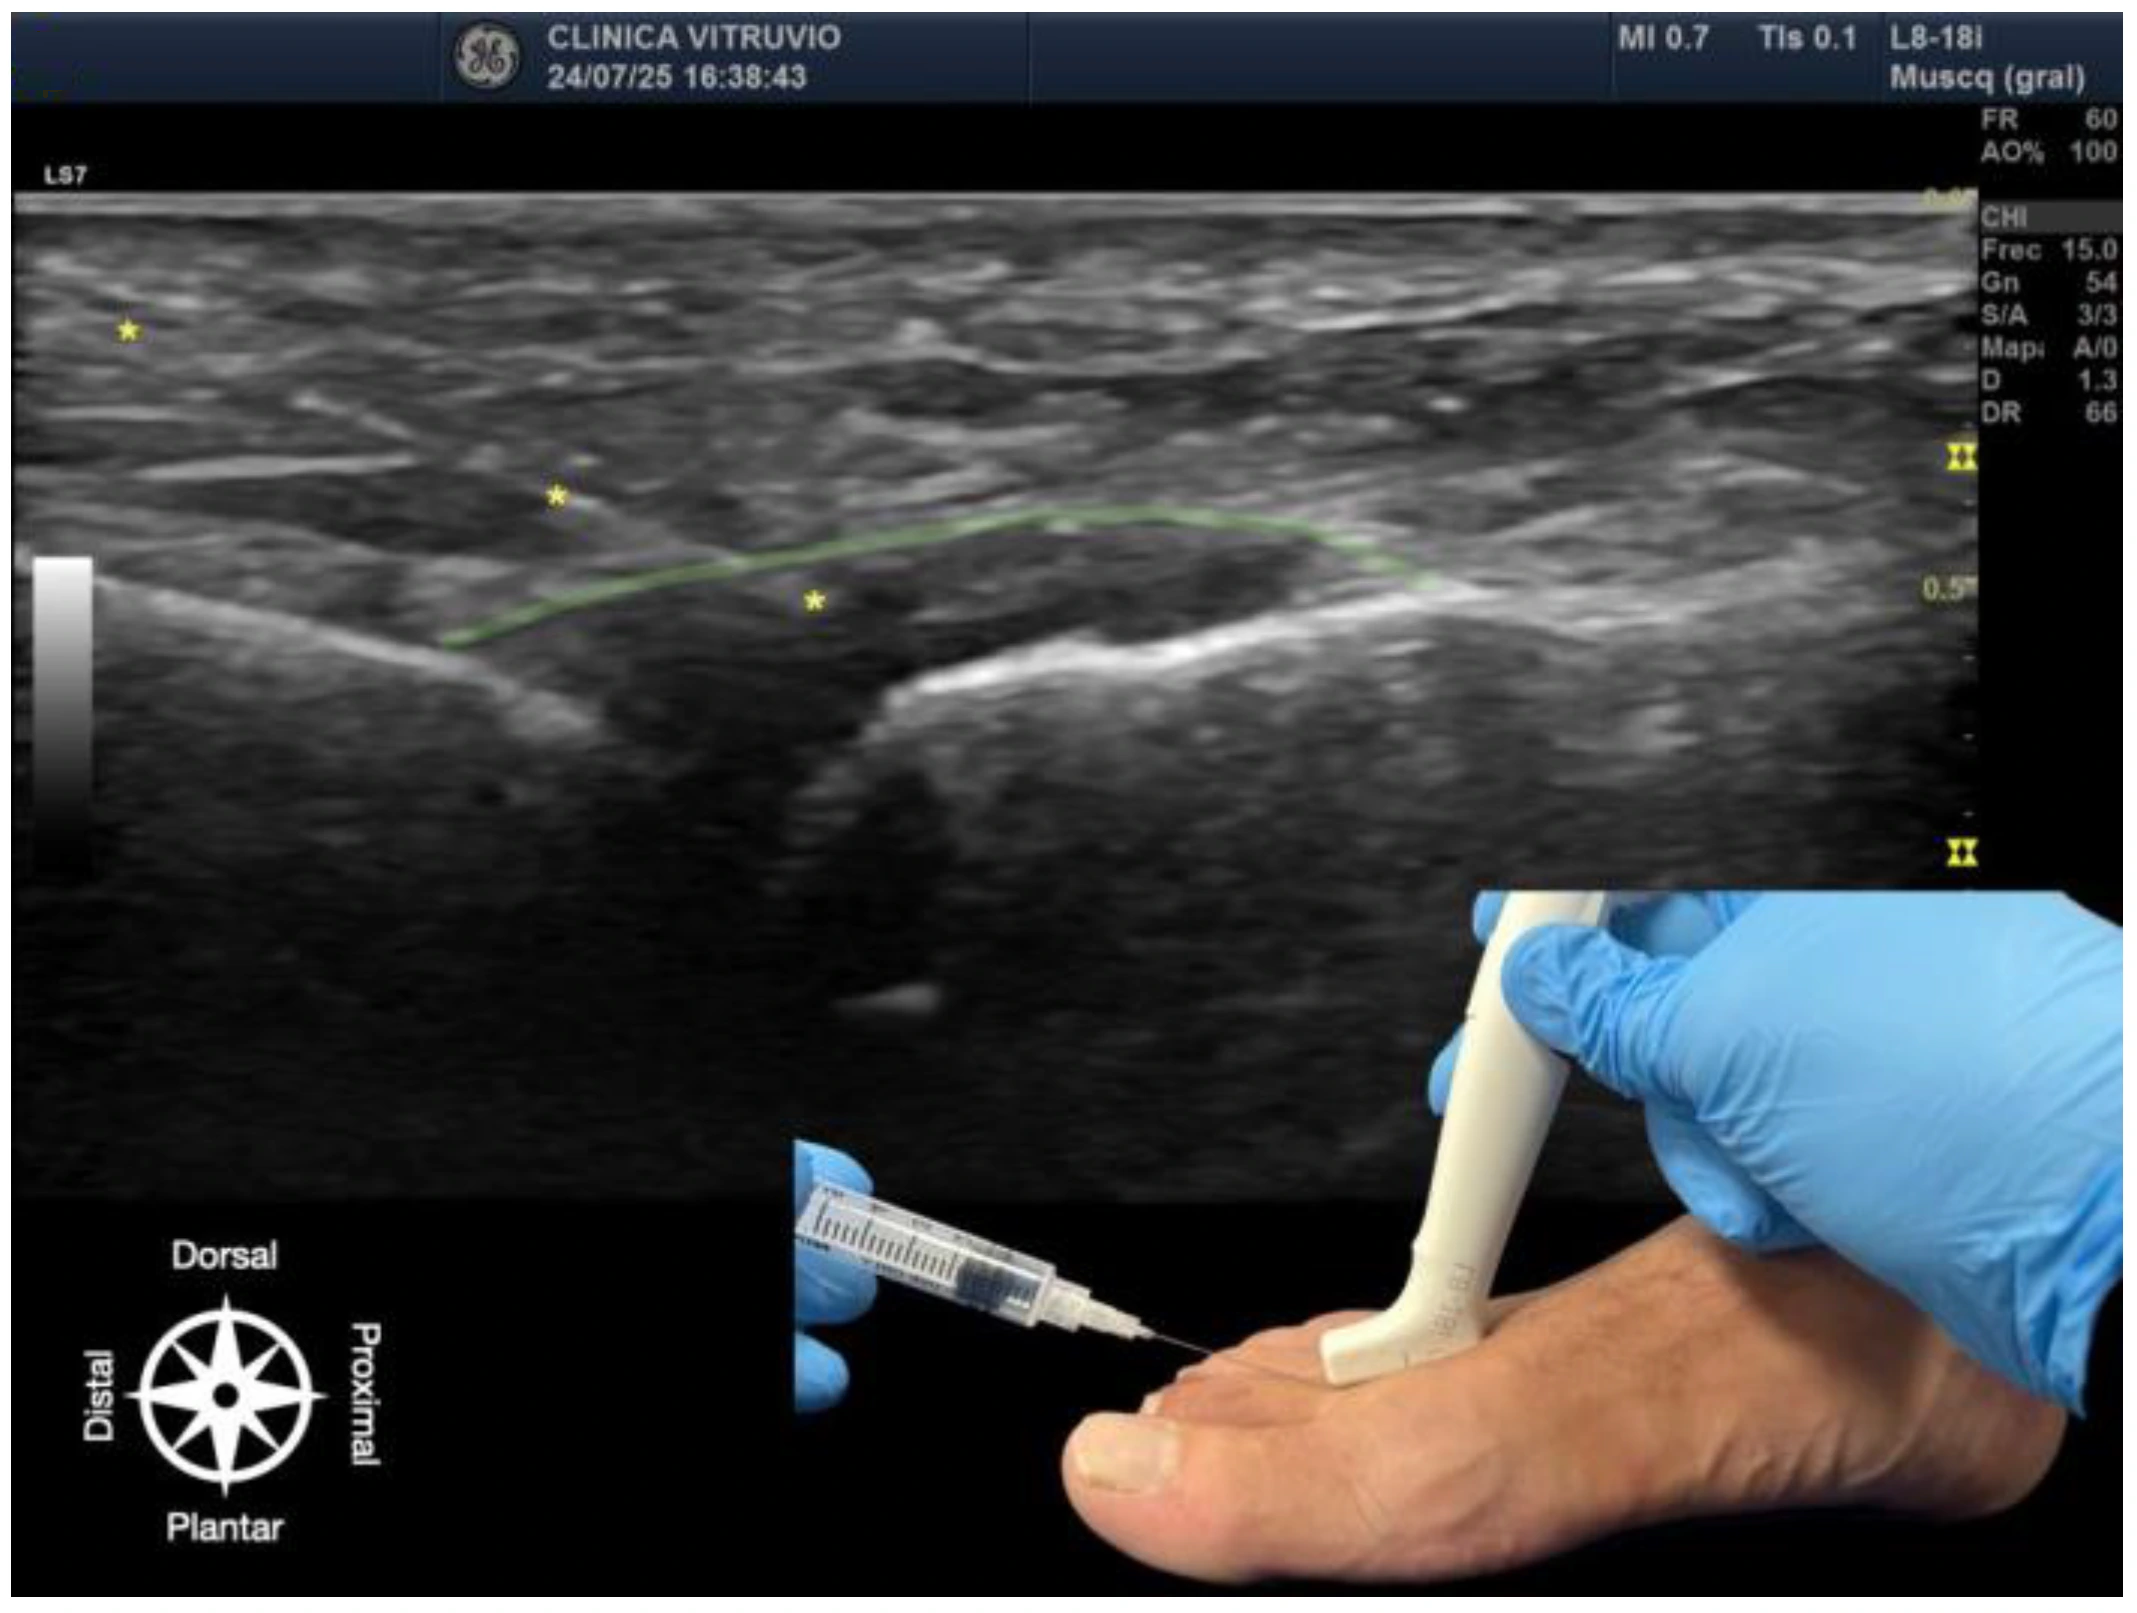

The procedure was performed using high-resolution ultrasound (10–15 MHz linear transducer) under real-time guidance (Figure 1 and Figure 2), following the selective infiltration protocol described by Ruiz Santiago et al. for Morton’s neuroma [3]. Three injections were performed on each anatomical specimen: 1—metatarsophalangeal joint of the third ray (3rd MTP joint), 2—metatarsophalangeal joint of the fourth ray (4th MTP joint), and 3—intermetatarsal space between the third and fourth rays (IM space).

A 25G, 40 mm needle was used. A volume of 1 cc of iodinated contrast medium (iopamidol 300 mg/mL) was injected at each site. For the MTP joints, a dorsal longitudinal approach was employed, with the needle oriented parallel to the metatarsal shaft and advanced to the base of the proximal phalanx, avoiding the dorsal capsule and extensor tendons. For the IM space, a transverse dorsoplantar approach was used. The needle was positioned in the deep plane of the intermetatarsal space, just beneath the deep transverse intermetatarsal ligament and above the course of the common plantar digital nerve.

Figure 1. Ultrasound-guided intra-articular infiltration of the metatarsophalangeal joint (Dorsal view). The joint capsule (dorsal recess) is highlighted in green, showing the needle, marked with an asterisk (*) in yellow, inside the articular space. In the lower right corner, the dorsal approach with probe and needle placement is displayed. The anatomical orientation diagram indicates the proximal–distal and dorsal–plantar axes.